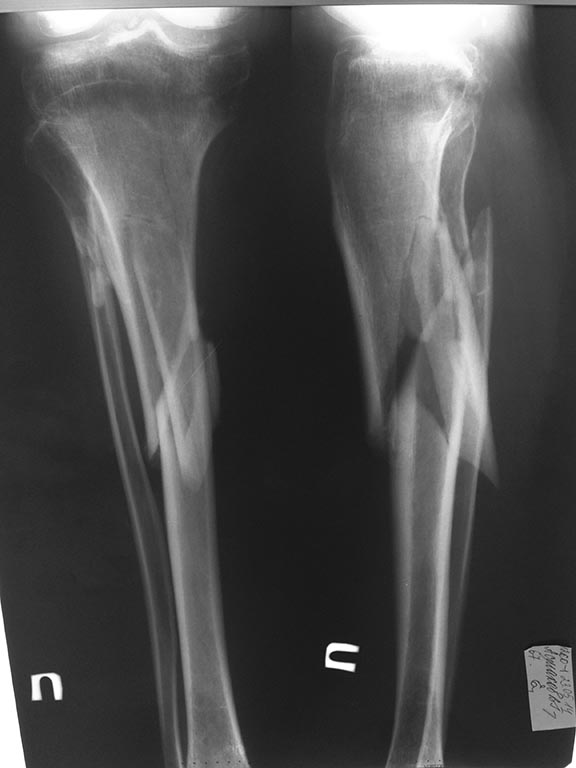

Поступил пациент 1947 г.р. Травма в январе 2014. Лечение консервативное - правая голень 1,5 месяца на ССВ, затем циркулярная гипсовая повязка; гипсовая лонгета на пятку, репозиции не было.Планируем оперировать,помогите с тактикой

голень сломана справа, а пятка слева. пациент ходит на костылях с опорой на левую ногу, правая в циркулярной гипсовой повязке. активных жалоб не предъявляет. доступны и пластины и гвозди

Для голени наверное наиболее оптимален БИОС. Перелом медиального мыщелка я бы не трогал.

Там еще мыщелок медиальный сломан... А по стопе неплохо бы КТ. Лучше бы с 3D моделированием.

Если вопрос касается стопы, то можно подождать, пятка неплохо компенсируется, возможно ничего делать и не придется. А голень оперируйте тем, чем лучше владеете, только не забудьте малоберцовую кость пересечь, она скорее всего срослась и помешает репозиции

Полагаю,необходимо проводить коррегирующий пяточно - таранный артродез для восстановления пяточно - таранных взаимоотношений, в случае, если позволяет состояние мягких тканей. В случае с голенью целесообразен БИОС пластиной с подъёмом импренированной части мыщелка.

Думаю, что на фоне перелома костей голени в проксимальной и средней трети перелом пяточной кости на данный момент меркнет. Корригирующую остеотомию можно и отложить и вернуться после лечения перелома голени - восстановление оси, длины и ротации в аппарате с последующей сменой фиксатора на внутри костный, дообследование мыщелков большеберцовой кости, их синтез. А пятка в конце этого пути.